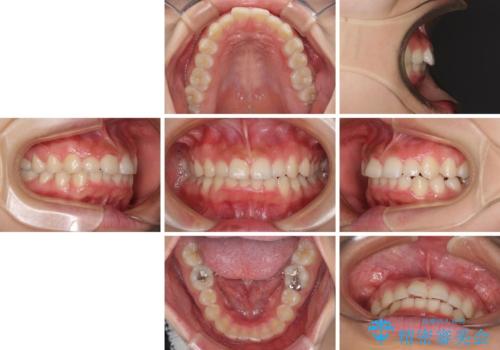

前歯のデコボコと突出感 インビザラインによる矯正治療

- 上下前歯のデコボコと、上顎前歯の突出感を気にして来院された患者様です。

インビザラインによる上下歯列の側方拡大と後方移動、IPR(歯と歯の間を削る)にるスペースの獲得により歯列を整えることとしました。

毎日22時間以上しっかりとマウスピースを装着していただいたので、スムーズに治療が進みました。歯と歯の間を削ることでうまくスペースコントロールでき、1年強で終えることができました。